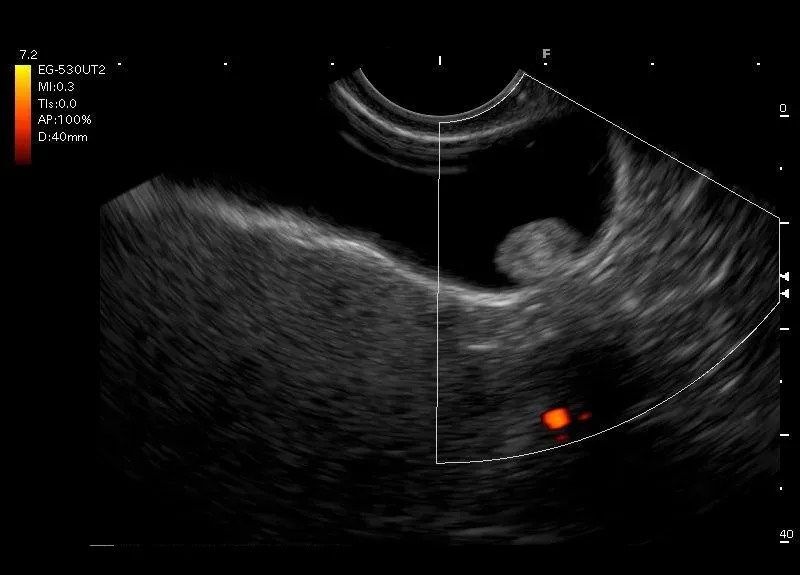

Owalna struktura przylegająca do ściany pęcherzyka żółciowego, bez cienia akustycznego, która nie zmieniła swojego położenia podczas próby wstrząsania- polip pęcherzyka żółciowego